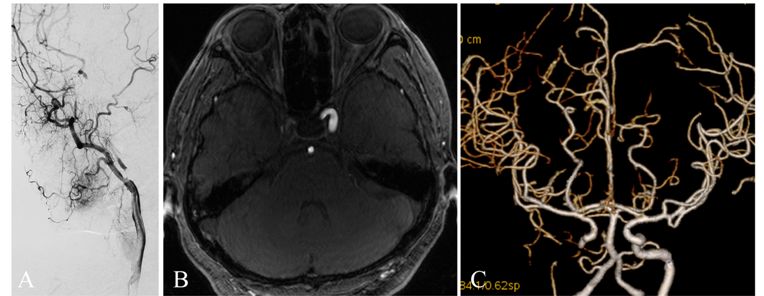

患者,女性,66岁。头晕伴左侧肢体阵发性无力5月。核磁检查显示右侧海绵窦以下血管闭塞

CTP:显示颅内灌注显示右侧半球低灌注

全麻下,血管造影显示右侧颈内动脉起始段完全闭塞,同侧眼动脉逆行充盈右侧颈内动脉,向近端反流到海绵窦上段同3月前的造影

先行颈动脉近端闭塞处切开并行内膜剥脱,再切口处置入动脉鞘后,用300cm 0.014微导丝交换出微导管用1.5mm×20mm gateway 行闭塞段扩张,造影显示右侧颈动脉闭塞段通畅

再使用3mm×20mm球囊行从上往下预扩张C2段三次,扩张后置入ENTERPRISE 支架4.5mm×28mm自膨支架两枚,经股动脉造影显示颈动脉全程完全畅通。复查CT未见新发梗死灶。